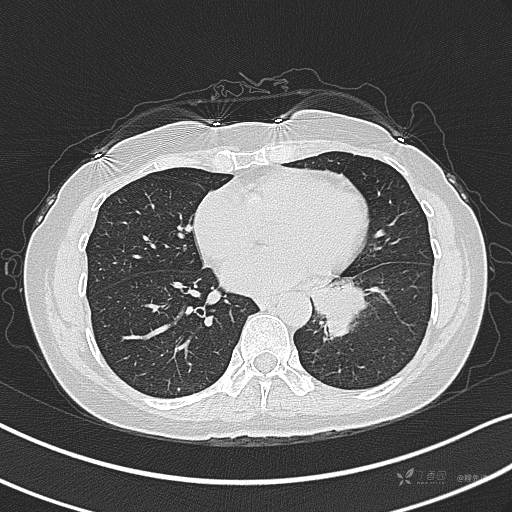

增强静脉期

静脉期CT值约84HU

CT值:平扫:31HU,动脉期:74HU,静脉期:84HU